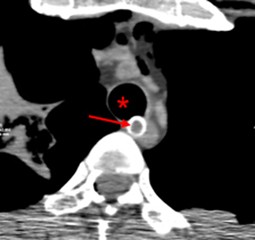

Es wird über den Todesfall einer 41-jährigen Patientin nach einer elektiven Unterkieferoperation berichtet. Die Patientin war nach einem endotrachealen Absaugmanöver reanimationspflichtig geworden. Bei operativ versorgtem Unterkiefer und postoperativer Gesichtsweichteilschwellung misslang die orotracheale Intubation, sodass ein chirurgischer Atemwegszugang geschaffen werden musste. Hierbei perforierte die eingeführte Trachealkanüle offenbar unbemerkt die Hinterwand der Trachea, und unter laufender Beatmung entwickelte sich ein Spannungspneumomediastinum mit Spannungspneumothorax. Diese wurden während der Reanimation nicht entlastet; die Reanimation blieb erfolglos. Der dargestellte Fall verdeutlicht die Notwendigkeit eines strukturierten Vorgehens bei Patienten mit Beatmungsproblemen unter kardiopulmonaler Reanimation, insbesondere hinsichtlich der Entlastung eines Spannungspneumomediastinums bzw. eines Spannungspneumothorax.

Tension pneumothorax can occur at any time during cardiopulmonary resuscitation (CPR) with external cardiac massage and invasive ventilation either from primary or iatrogenic rib fractures with concomitant pleural or parenchymal injury. Airway injury can also cause tension pneumothorax during CPR. This article presents the case of a 41-year-old woman who suffered cardiopulmonary arrest after undergoing elective mandibular surgery. During CPR the upper airway could not be secured by orotracheal intubation due to massive craniofacial soft tissue swelling. A surgical airway was established with obviously unrecognized iatrogenic tracheal perforation and subsequent development of tension pneumomediastinum and tension pneumothorax during ventilation. Neither the tension pneumomediastinum nor the tension pneumothorax were decompressed and accordingly resuscitation efforts remained unsuccessful. This case illustrates the need for a structured approach to resuscitate patients with ventilation problems regarding decompression of tension pneumomediastinum and/or tension pneumothorax during CPR.